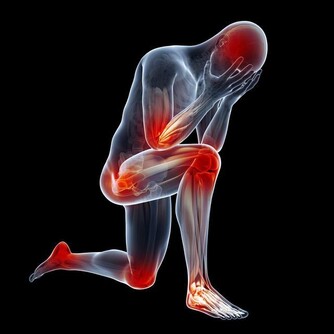

10. 它有助於預防腎結石

腎結石通常由於脫水而出現,所以檸檬水的好處之一是可以幫助沖洗腎臟,

來自檸檬的酸可以防止這些導致疼痛的晶體沉積。

而且,排尿增多也有助於預防腎結石。